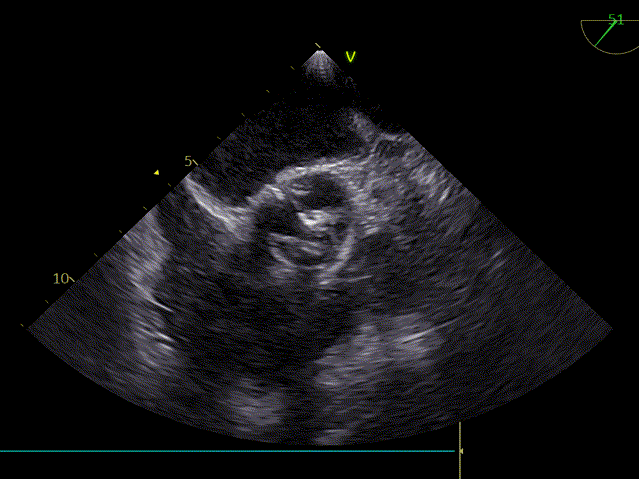

术前超声心动图:

主动脉瓣狭窄(重度,跨瓣平均压差69mmHg),房颤、心衰,反复住院2年;瓣环直径2.4cm,AV 5.0m/s EF 59%。

TEE45度检查左心耳